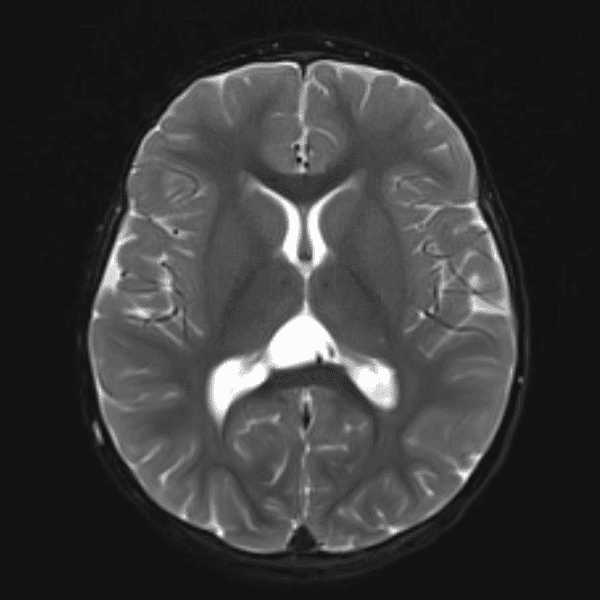

Classic Cases